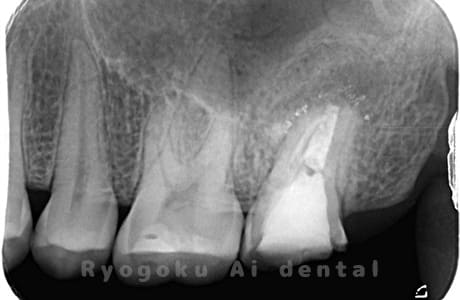

術前

-

歯根端切除術後

術後1年

- 原因

- 歯根嚢胞

- 治療内容

- 歯根端切除法

- 治療費用

- ¥77,000

他院で行った根管治療後、腫れがひかないためにご来院された患者様です。歯根端切除を行い、現在、経過良好です。